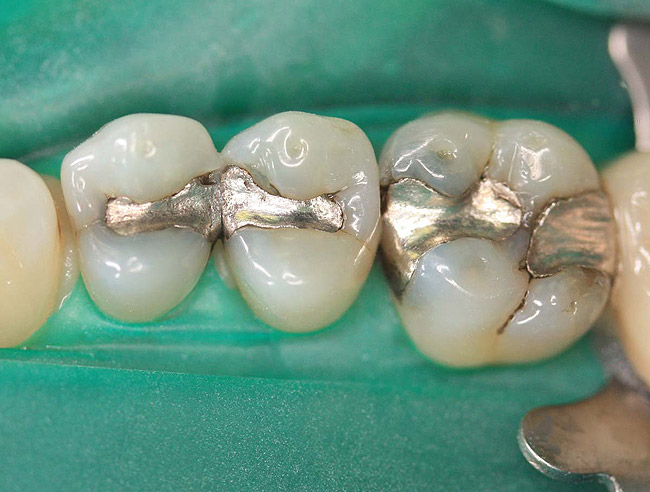

Case 2 (Figure 7 through Figure 11) depicts a series of defective amalgams on the first molar and biscupids. The amalgams were removed, the decay was excavated and cracks were eliminated. Bonding was completed on dentin and enamel. The teeth were matrixed and composite was built with layering techniques. To control contours, each tooth was completed individually, and then the next one was done. Composite was shaped, occlusal adjustment was completed, and final polishing was done.

Figure 8. Teeth after removal of amalgams.

Figure 8

Figure 9. Prepared teeth after removal of decay and cracks.

Figure 9